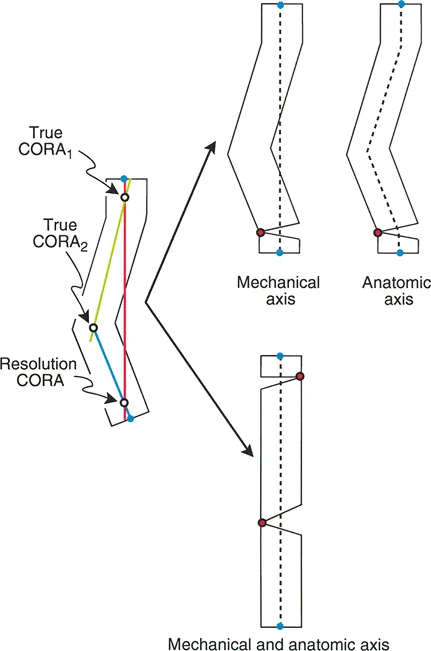

تحدي مركز دوران الانحراف (CORA) القريب من المفصل

لمطابقة مفصلة المثبت الخارجي مع المستوى الدقيق لمركز دوران الانحراف (CORA)، يجب غالبًا بناء المفصلة فوق أو تحت مستوى الحلقة الفعلية. يُعرف هذا في مبادئ بالي باسم تجميع المفصلة القريبة من المفصل (juxta-articular hinge assembly).

إذا كان مركز دوران الانحراف (CORA) يقع بالقرب من خط المفصل، فإن وضع حلقة إليزاروف القياسية عند هذا المستوى بالضبط مستحيل دون انتهاك مساحة المفصل أو شد الهياكل الكبسولية الحيوية. لذلك، يتم تثبيت الحلقة المرجعية بالعظم الكثيف أو العظم الطويل المتاح، ويتم بناء آلية المفصلة باستخدام قضبان ملولبة، ولوحات توصيل، ودعامات. ثم يتم "إنزالها" (أو رفعها) لتتطابق تمامًا مع مركز دوران الانحراف (CORA) الهندسي الحقيقي.

قواعد بالي لقطع العظم (Osteotomy Rules) في وضع الأجهزة

فهم قواعد بالي لقطع العظم أمر لا غنى عنه لتخطيط الإطار:

- قاعدة قطع العظم 1: عندما يمر قطع العظم ومحور تصحيح الانحراف (ACA) كلاهما عبر مركز دوران الانحراف (CORA)، فإن نهايات العظم ستنحرف دون ترجمة (انزياح). يتم استعادة المحور الميكانيكي، وتظل نهايات العظم متقاربة تمامًا، مما يخلق تصحيحًا كلاسيكيًا "إسفينيًا مفتوحًا" أو "إسفينيًا مغلقًا".

- قاعدة قطع العظم 2: عندما يمر محور تصحيح الانحراف (ACA) عبر مركز دوران الانحراف (CORA)، ولكن يتم إجراء قطع العظم على مستوى مختلف (غالبًا بسبب ضعف جودة العظم عند CORA أو مشاكل في الجلد)، فإن نهايات العظم ستنحرف وتخضع لترجمة محسوبة ومقصودة لإعادة محاذاة المحور الميكانيكي.

- قاعدة قطع العظم 3: (للاكمال) عندما يمر قطع العظم عبر مركز دوران الانحراف (CORA)، ولكن يتم وضع محور تصحيح الانحراف (ACA) خارج CORA، سيتم إنشاء تشوه ترجمة جديد، وهو خطأ شائع في وضع المفصلات غير المخطط له جيدًا.

في المنشآت القريبة من المفصل، غالبًا ما نعتمد على قاعدة قطع العظم 2. نظرًا لأنه لا يمكننا قطع العظم بأمان عند خط المفصل تمامًا (مركز دوران الانحراف CORA)، فإننا نقطع العظم في مستوى أدنى في منطقة الميتافيسيس. بعد تحقيق التصحيح الزاوي عبر المفصلات (محور تصحيح الانحراف ACA)، يتم إعادة محاذاة خطوط المحور الميكانيكي بشكل مثالي، ولكن نهايات العظم في موقع قطع العظم تتحرك بالنسبة لبعضها البعض.